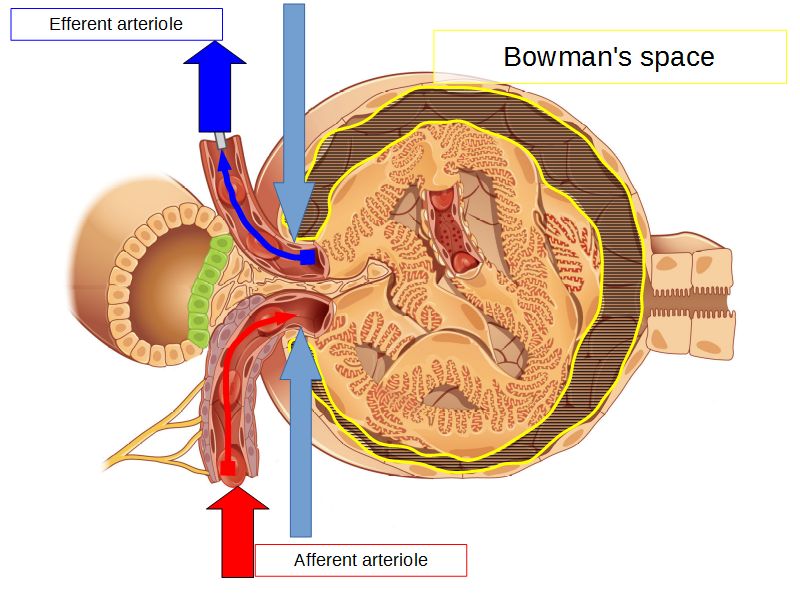

Blood flow

- Efferent arteriole

- Smooth muscle in media

- Capillaries

- Fenestrated

- Afferent arteriole

- Smooth muscle in media

- Capsular space